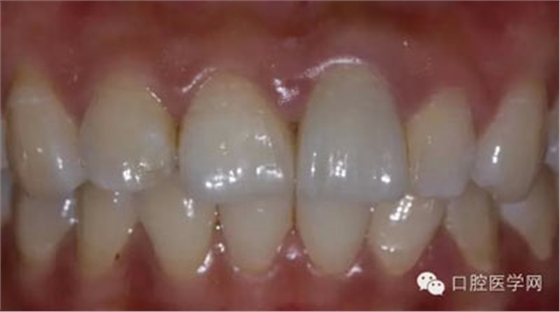

5、3MU200樹(shù)脂粘接劑粘固全瓷冠術(shù)后照

6、術(shù)后一周照,牙齦恢復(fù)良好

7、術(shù)后照飽和度調(diào)到最低與最高,觀察牙齒修復(fù)后的明度及飽和度

8、術(shù)前術(shù)后對(duì)比